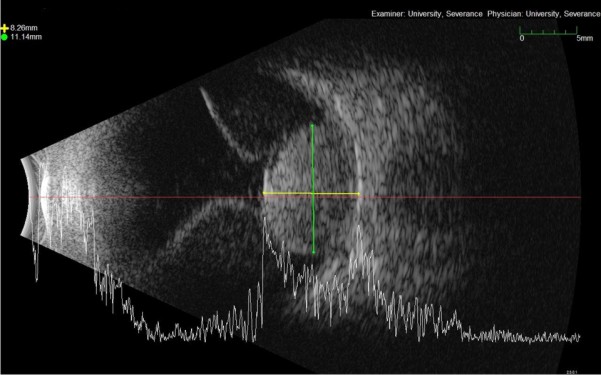

¸Æ¶ô¸· Èæ»öÁ¾Àº ¾È±¸³» ¹ß»ýÀ§Ä¡¿¡ µû¶ó ´Ù¸£Áö¸¸ Ãʱ⿡´Â ÀϹÝÀûÀ¸·Î ¾È°úÀû Áõ»óÀ» µ¿¹ÝÇÏÁö´Â ¾Ê´Â´Ù. ÇÏÁö¸¸ Á¾¾çÀÌ ÁøÇàÇÏ¸é¼ ÀÌÂ÷ÀûÀÎ ¸Á¸·¹Ú¸® ¹× ¸Á¸·ÇÏ¾× µî¿¡ ÀÇÇØ ½Ã¾ß°á¼ÕÀ̳ª ½Ã·ÂÀúÇÏ µîÀÇ Áõ»óÀÌ »ý±æ ¼ö ÀÖ´Ù. ÁøÇàÇÒ °æ¿ì ºÒ·èÇÑ µ¼ ¸ð¾ç(dome shaped)ÀÇ À¶±âµÈ º´º¯À¸·Î Ä¿Áö¸ç, ¹ö¼¸ ¸ð¾ç(mushroom-shaped)À¸·Î º¸À̱⵵ ÇÑ´Ù.

¸Æ¶ô¸· Èæ»öÁ¾Àº ȸ»öÀ̳ª °¥»öÀÇ Á¾¾çÀÌ ¸Á¸· ¹Ø ¸Æ¶ô¸· ºÎÀ§¿¡ À§Ä¡Çϸç, ´ë°³ 2mm ÀÌ»óÀ¸·Î µÎ²®´Ù. ¸Á¸· ¾Æ·¡¿¡ ¹°ÀÌ Â÷´Â ¸Á¸·ÇϾ×ÀÌ µ¿¹ÝµÇ´Â °æ¿ì°¡ ¸¹À¸¸ç, Àå¾×¼º ¸Á¸·¹Ú¸®¸¦ µ¿¹ÝÇϱ⵵ ÇÑ´Ù. ¿À·»Áö»ö »ö¼ÒÄ§ÂøÀÌ µ¿¹ÝµÉ ¼ö ÀÖÀ¸¸ç, ¸Æ¶ô¸· Èæ»öÁ¾¿¡ Ç÷¾×À» °ø±ÞÇÏ´Â Ç÷°üÀÌ ÈòÀÚÀ§¿¡¼ º¸À̱⵵ ÇÑ´Ù. Å©±â°¡ Å« ¸Æ¶ô¸· Èæ»öÁ¾Àº ´«ÀÇ ±¸Á¶¸¦ º¯Çü½ÃÄÑ ³ì³»ÀåÀ» À¯¹ßÇÒ ¼öµµ ÀÖ´Ù.